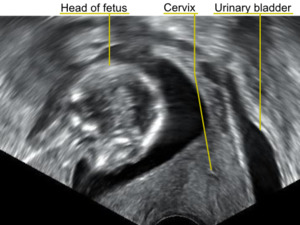

A transvaginal ultrasound showing a retroverted uterus during pregnancy. The cervix lies posteriorly to the urinary bladder, and the uterus normally extends superiorly from it, but the direction of the body of the fetus reveals that the uterus extends backwards.